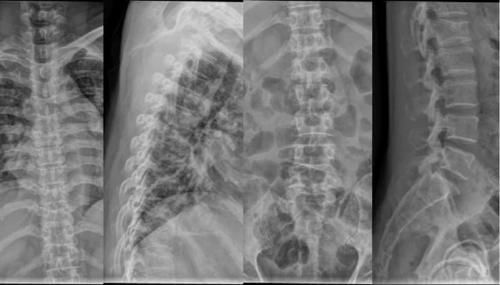

Osteoblastoma 骨母细胞瘤

好发于10~20y,颈椎多见,多位于椎体的椎板、横突、棘突

囊状膨胀性骨质破坏,内有细沙洋钙化、骨化,周围有硬化边

可合并ABC

Case18:M,16y;双下肢乏力及麻木感40余天。

文章插图